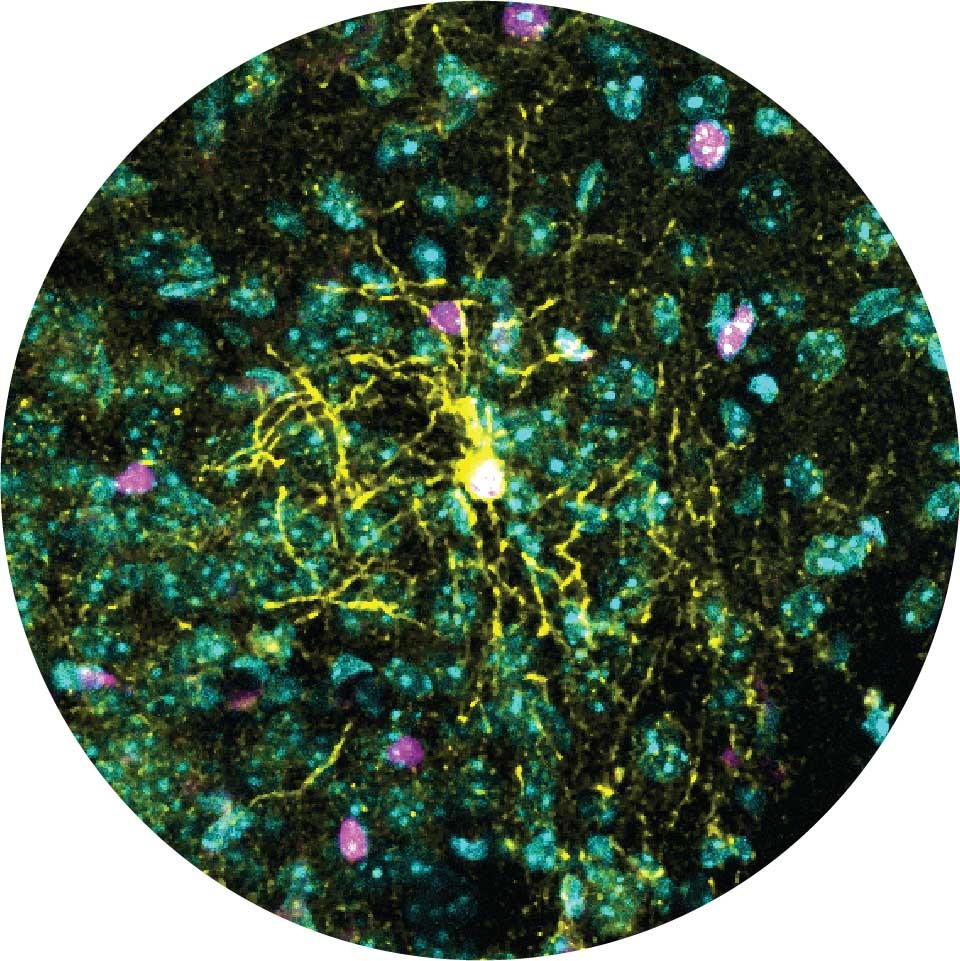

Ученые из лаборатории профессора Алона Чена в Институте Вейцмана, которая специализируется на изучении реакции организмов на стресс, пишут: «Мы направили наиболее чувствительную исследовательскую линзу на область мозга, которая действует как центральный узел стрессовой реакции у млекопитающих, - паравентрикулярное ядро (PVN) гипоталамуса», — объяснила доктор Елена Бривио.